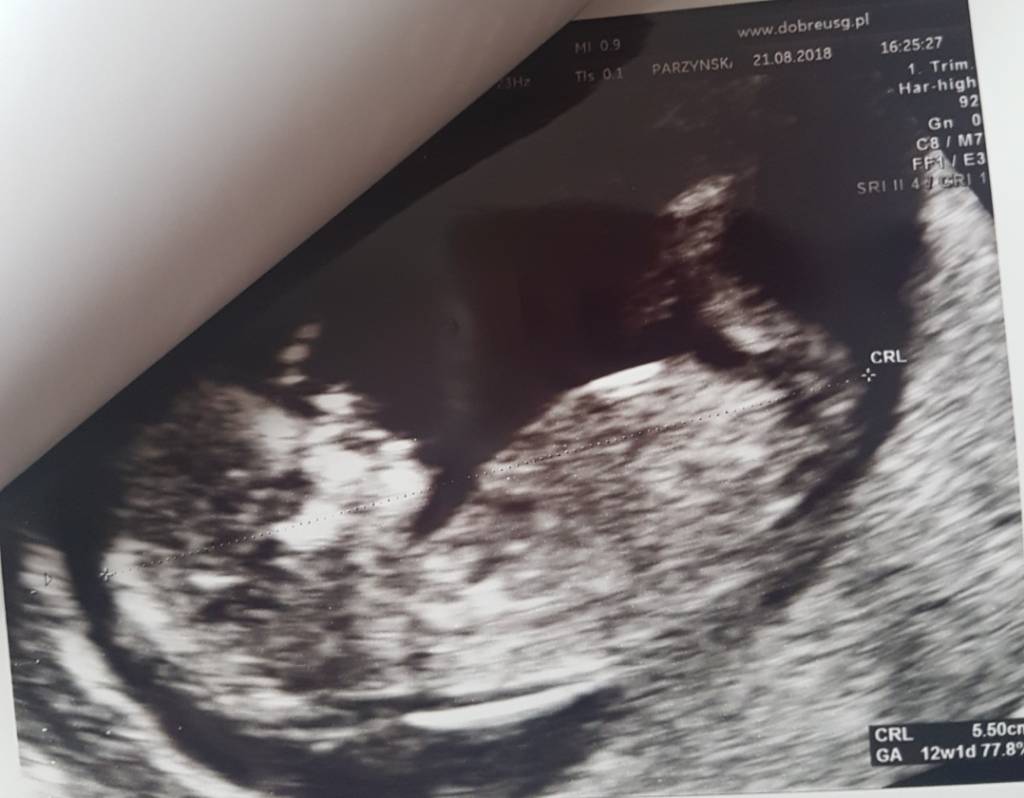

cudowna wiadomość że dzieciątko zdroweDziewczyny, jest dobrze [emoji4] maluch ma teraz 5,5cm [emoji173] serduszko ladnie bije 159bpm, pepowina trojnaczyniowa [emoji7]

Ryzyka skorygowane wyszly niskie[emoji173]:

Tr. 21. 1:7213

Tr. 18. 1:6995

Tr. 13. <1:20000

Kosc nosowa obecna [emoji7]

Ocena wczesnej anatomii - budowa, przeplywy, wszystko ok, nie bede Was zameczac szczegolami [emoji4]

Rozmawialismy z Pania Dr i sama stwierdzila, ze pomimo bardzo dobrych wynikow z dzisiejszych badan, to jesli mozemy, glownie biorac pod uwage in vitro, zalecalaby jednak zrobic wolne dna plodowe. I tak bylismy zdecydowani na Nifty, wiec umowilam sie na pobranie krwi na przyszly tydz. Nastepna wizyte w tej miejscowce u docenta mam 12.09, wtedy juz powinny byc wyniki z dna plodowego, wiec wszystko bedzie wiadomo napewno.

Aaa co do plci na podstawie wyrostka wydaje sie ze to dziewczynka [emoji7] ale Pani Dr mowi ze ten wyrostek taki nie calkiem lezacy, wiec dzidzius moze nas jeszcze zaskoczyc i w ktoryms momencie sie pojawic siusiaczek [emoji4]